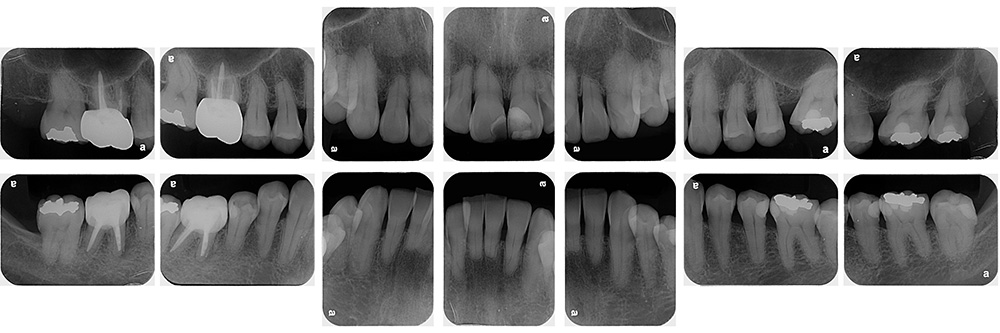

術前

術後

世代・性別

40代女性

主訴

歯が揺れている気がするので見てほしい

治療内容

ブラッシング指導、歯周基本治療

治療期間

4ヶ月

治療費

保険適応内

治療のリスク

一時的に歯ぐきからの出血や痛み、歯のしみ(知覚過敏)が起こることがある